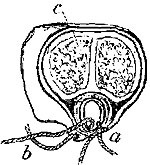

Ligature above Omohyoid.—Using the anterior border of the sterno-mastoid as a guide, but leaving it gradually above to a little nearer the mesial line, an incision (Plate IV. fig. 1), varying in length according to the depth of fat and cellular tissue in the neck, but with its central point opposite the upper border of the cricoid cartilage, must be made through skin, platysma, and superficial fascia. While making the incision the head should be held back, and the face slightly turned to the opposite side; the parts being now relaxed by position, the edges of the wound must be held apart by blunt hooks or copper spatulæ, and the deep fascia carefully divided over the vessel, which will be recognised by the pulsation. It may be noted here that even in thin subjects the sterno-mastoid edge invariably overlaps the vessel, though in many anatomical diagrams it would appear to be in part subcutaneous.

The sheath of the vessel is then to be cautiously opened to the extent of about half an inch. The internal jugular vein, possibly much distended, may overlap the artery on its outer side, and will require to be pressed, emptied, and held out of the way. A small portion of the artery being thoroughly separated from the sheath, the aneurism-needle must be passed from without inwards to avoid the vein, and keep as close to the artery as possible to avoid the vagus.

Ligature of Carotid below the Omohyoid.—An incision in precisely the same direction as the former, but at a slightly lower level, is required, but the dissection is rather more difficult. The edge of the sterno-mastoid when exposed must be drawn outwards; the sterno-hyoid and thyroid inwards; the omohyoid upwards; the sheath opened, and the descendens noni or its branches drawn to the tracheal side. The jugular vein and vagus are both at the outer side, and must be avoided, while the inferior thyroid artery and sympathetic nerve both lie behind the vessel, and may be included in the ligature if care be not taken.

Varieties.—Sedillot's Operation.—To secure the artery still lower in the neck: An incision two and a half inches long, from the inner end of the clavicle obliquely upwards and outwards in the interval between the sternal and clavicular attachments of the sterno-mastoid; this divides the superficial textures; the two portions of muscle must then be drawn apart. The internal jugular vein lies in the interval, and must be drawn to the outside before the artery can be seen at all, and it is this that makes this operation very difficult and dangerous, especially on the left side, where the vein is close to the artery, and probably even crossing it from left to right. The thoracic duct is behind.

Malgaigne's modification of the above is an improvement: to expose the external attachment of the muscle, to cut it through and turn it to the outside, as in the operation for ligature of the innominate, then to divide or pull inwards sterno-hyoid and sterno-thyroid, thus exposing the sheath. The needle must be passed from without inwards.